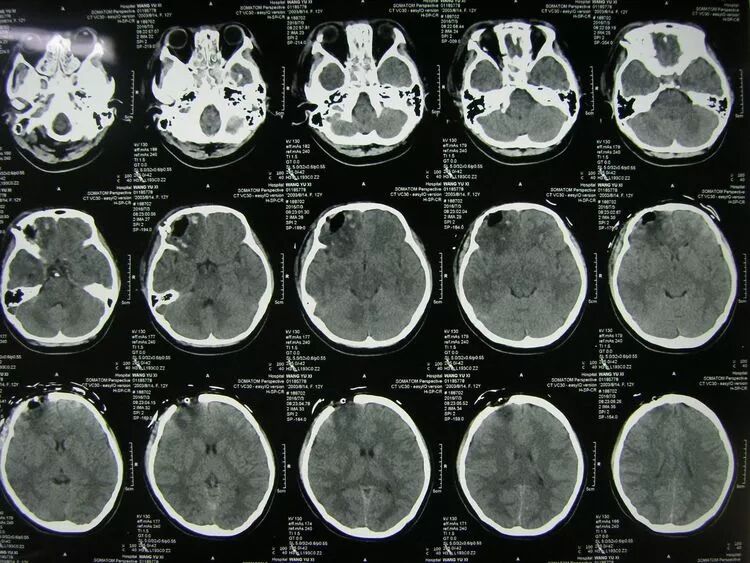

骨窗片显示额骨及颅底骨粉碎骨折

术后1天CT复查,止血减压良好,基底池清晰,中线居中,患儿神志转清。